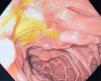

En la exploración física, el catéter Foley provisional estaba migrado distalmente, y la movilización, rotación e intentos de retiro de la sonda, exacerbaban el dolor abdominal. En la tomografía computarizada (TC) se observó el catéter Foley migrado en yeyuno proximal, con datos tempranos de isquemia intestinal (figs. 1 y 2). Se realizó cirugía de urgencia encontrando una intususcepción a 50 centímetros del ángulo de Treitz, secundaria a la migración del catéter Foley.

Los datos macroscópicos de isquemia intestinal observados durante la laparotomía, se resolvieron inmediatamente después del retiro del catéter y liberación manual de la intususcepción intestinal. Por este motivo, se optó por no resecar el segmento de intestino involucrado (fig. 3). Posteriormente, se le realizó al paciente una endoscopia, durante la cual se observaron 2 úlceras en la segunda porción del duodeno, posiblemente relacionadas con la migración del catéter. Se colocó una sonda GEP 24Fr mediante técnica de arrastre (PULL) (fig. 4). Se inició terapia estándar con inhibidor de la bomba de protones para cicatrización de las úlceras. En su visita de seguimiento más reciente, 7 meses tras la recolocación GEP, el paciente presentó falla en la prueba de deglución de líquidos, por lo que requirió una combinación de dieta oral y alimentación por sonda GEP. El paciente, al momento de la redacción del presente reporte, continuaba con ejercicios de rehabilitación de la deglución y fisioterapia.